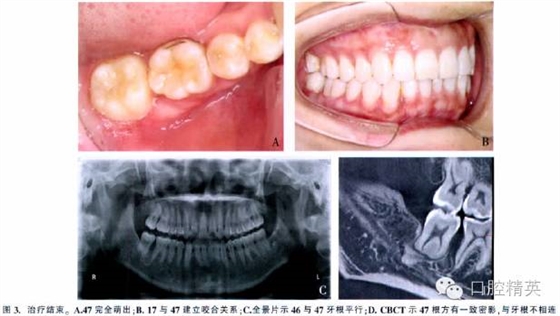

總療程為9.5個月。47牙周附著水平正常,與對牙合牙咬合關系良好。頭影測量顯示治療前、后下頜平面角和面下1/3高度無明顯變化。CBCT示右后牙牙根平行,47牙根長度及根形未發(fā)生變化(圖3)。